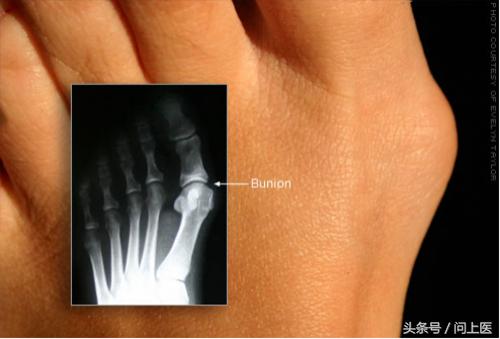

问题7:拇囊炎

患拇囊炎时,连接大拇指的骨头肿大而向外突出,这会导致脚骨头不正,引发关节炎而疼痛,也可能导致鸡眼。

拇囊炎多出现在长期穿高跟鞋的女士脚上。

止痛药、定制的鞋垫或手术治疗可能有帮助。应穿宽松的鞋子并避免穿高跟鞋。